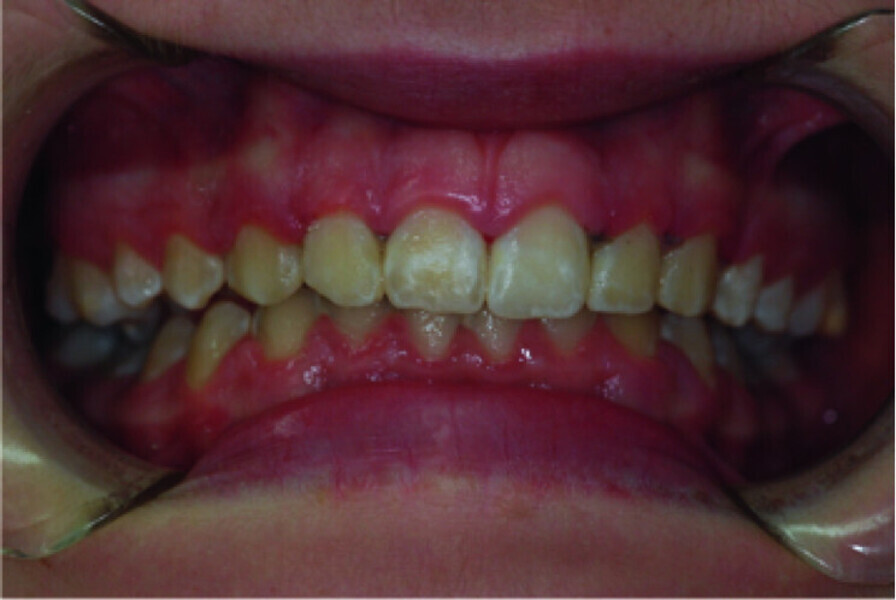

Use of diode laser in the treatment of gingival enlargement during orthodontic treatment